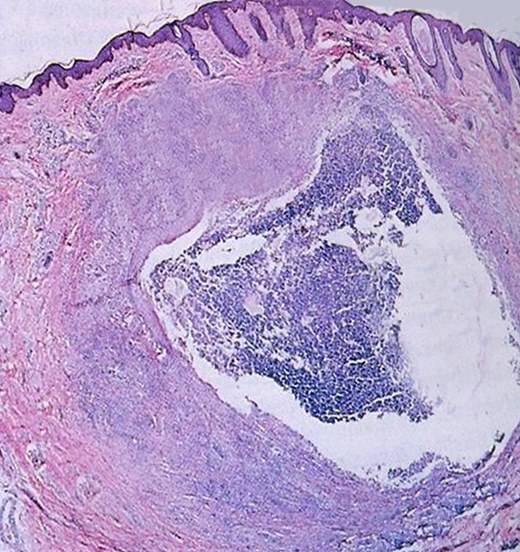

여드름은 ‘모낭 피지선 단위’라고도 하는데, 이는 피지선과 피지가 배출되는 통로인 모낭 상층부에서 발생한다. 이는 신체 호르몬의 불균형이 찾아오거나 막힌 모공입구, 여드름 균의 증식으로 발생한다고 알려져 있다.

(사진출처:더3.0피부과, w스타뉴스 DB)